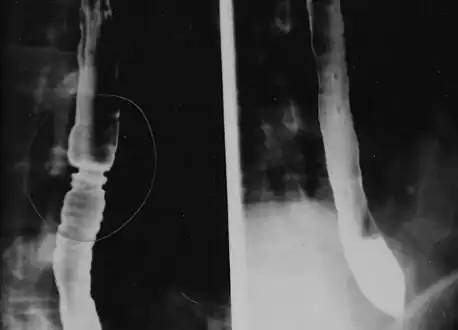

The barium swallow of the esophagus on the left side shows multiple rings associated with eosinophilic esophagitis.

Radiologically, the term "ringed esophagus" has been used for the appearance of eosinophilic esophagitis on barium swallow studies to contrast with the appearance of transient transverse folds sometimes seen with esophageal reflux (termed "feline esophagus").[17]